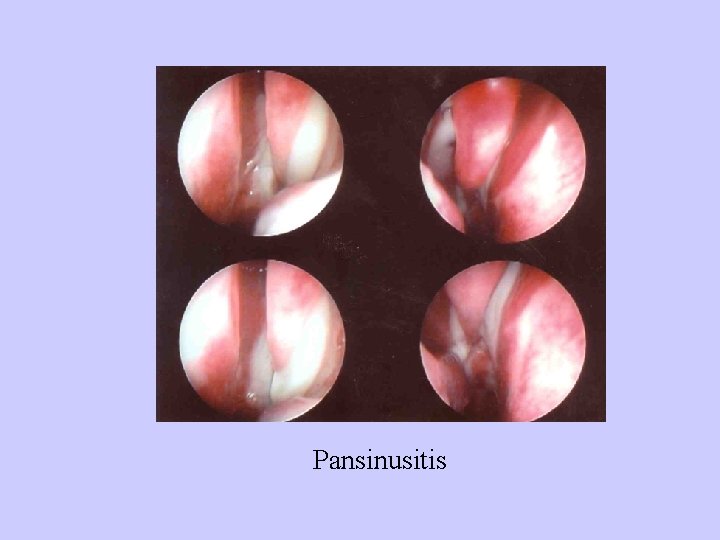

Pansinusitis

Pansinusitis